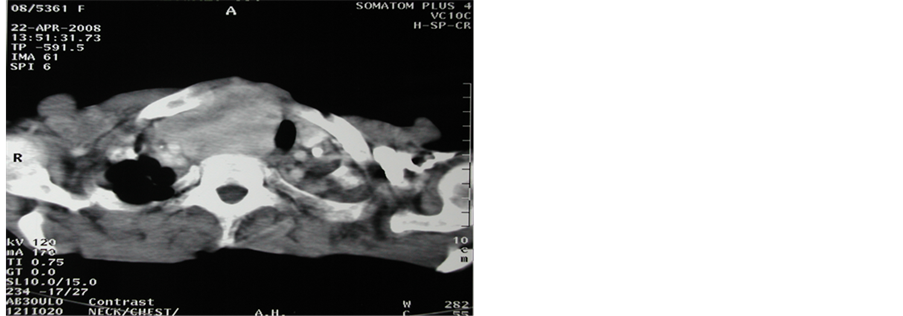

Figure 2. One of our patients with superior mediastinal syndrome with CT scanning (axial view) showing the huge RG.

Ultrasound can suspect a RG when their inferior margins are not visualized. CT scanning of the neck and upper chest gives a bright view of the extension and appreciates the size, content and relations with mediastinal vessels, trachea and the esophagus. MRI allows multiplanar views. In this study, CT scanning was the investigation of choice done in 40 patients (95.2%) and was conclusive for the preoperative anatomical planning for surgery [8] [13] .